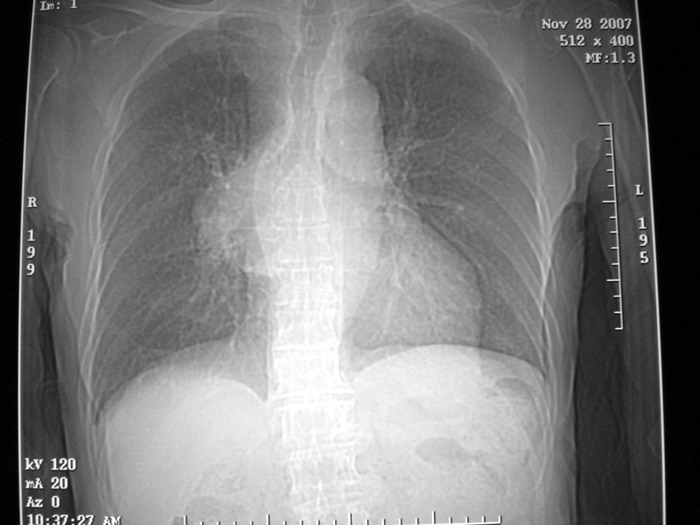

m、70y,反复咳嗽2月。请各位同仁给定位1、(肺?,纵隔?)2、定性。感谢!!

正位看,支气管分叉角度增大,来源考虑后纵隔的占位,性质考虑1.神经源性肿瘤2.肿大淋巴结

右下肺纵隔旁较大 均匀密度肿块,部分边缘植入纵隔,气管明显受压 变形。支持:后纵隔肿瘤!首选:神经源性!不支持肺内肿瘤原因:1 肿瘤位于下叶支气管及背段支气管开口区,但未侵犯支气管,只是受压表现。2 纵隔内未见肿大淋巴结。3 肺内未见阻塞性肺炎。